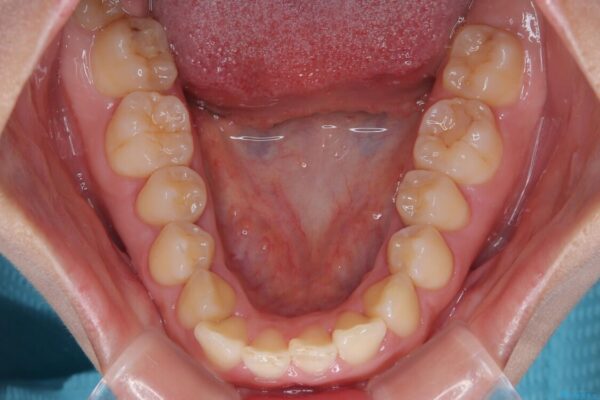

治療途中

• 目立ちにくい表側装置で1年完了!狭いアーチを側方拡大し前歯のデコボコを整えた症例 治療途中画像